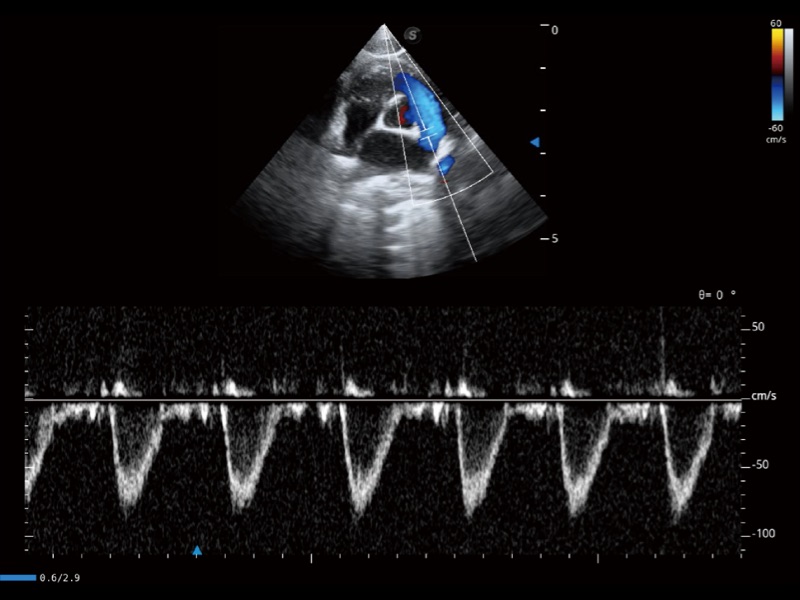

通过创新的 Matrix E自适应滤波器和超长时间域算法,极大提升超低速微细血流的检出能力,同时更精准地滤除软组织和噪声信号,为兽用医生提供以往无法通过常规血流获得的疾病诊断信息。

通过色彩血流和实时宽景相结合,可观察到完整的静脉或动脉的血流,方便医生检查。实时扫查过程中,如有任何操作失误也可以很容易地进行回扫擦除,而不会中断扫查。